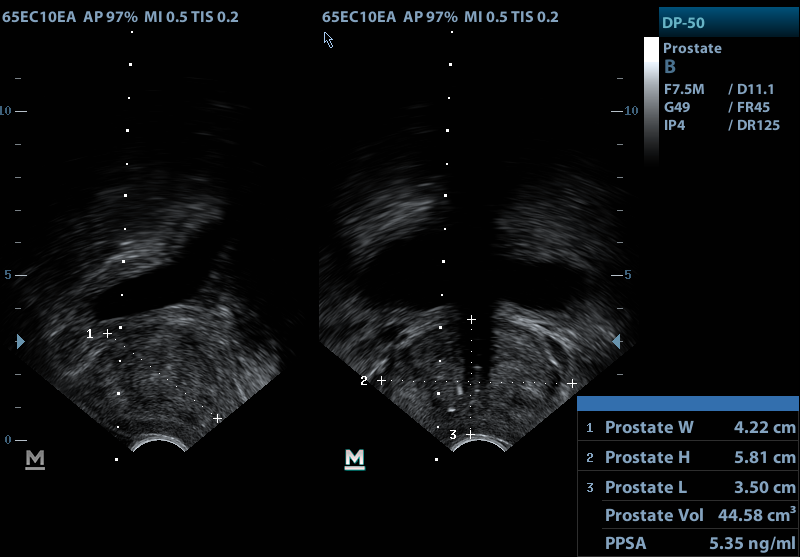

Or, you can choose another section to learn more about a specific question you have. The american cancer society provides detailed information on prostate cancer and its treatment. Drawing of a transrectal ultrasound with prostate biopsy, showing a needle and needle guide inserted in the rectum. Learn more about prostate cancer basics at discovery health. A new procedure using ultrasound techniques may soon be available to treat prostate cancer without the complications of surgery.